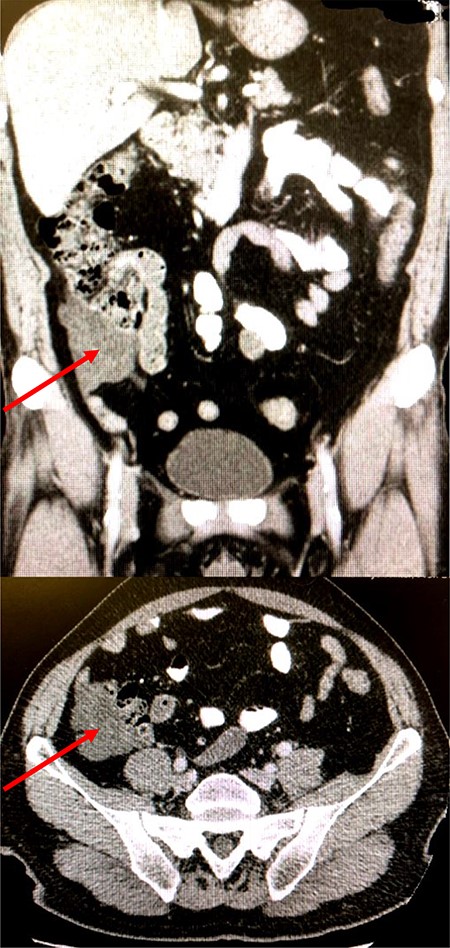

A commuted tomography (CT) scan was performed in an outside institution, which demonstrated a 6.6-cm cystic mass between the sigmoid colon and caecum (Fig. 1). A subsequent colonoscopy yielded four small polyps, but the endoscope could not pass beyond the hepatic flexure. As the patient was minimally symptomatic, an interval CT scan was performed four months following initial presentation to re-assess the dimensions of the lesion. This showed no change in size with a persistent cystic mass in the right iliac fossa (Fig. 1). Following a lengthy discussion with the gentleman and his family regarding options including surgery versus a watchful wait approach with interval scanning, the patient chose to undergo elective resection.